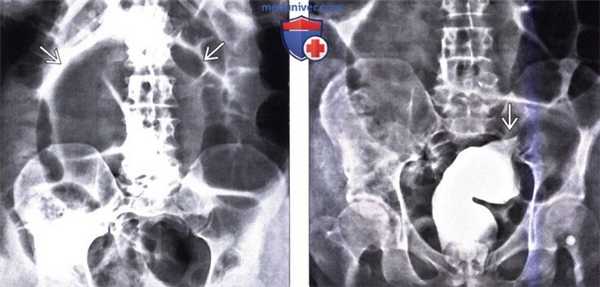

(Слева) При рентгенографии выполненной мужчине 65 лет с жалобами на боль и вздутие живота, визуализируется увеличенная, растянутая сигмовидная кишка, выглядящая как перевернутая буква, «ножки» которой начинаются в проекции таза, что является характерным признаком заворота.

(Справа) На рентгенограмме в прямой проекции, полученной в положении лежа на спине во время ирригоскопии этому же пациенту, определяется сужение просвета кишки в виде «птичьего клюва». Такая конфигурация типична для заворота сигмовидной кишки.

(Справа) На «разметочной» цифровой рентгенограмме, полученной в положении лежа на спине в передне-задней проекции у мужчины 89 лет, длительное время находящемся в доме престарелых, которого в течение двух последних дней беспокоила сильная боль в животе в сочетании со значительным его вздутием, определяется выраженная дилатация сигмовидной кишки, а также восходящей и нисходящей ободочной кишки. Обратите внимание на плотно прилежащие друг к другу стенки сигмовидной кишки.

(Справа) На аксиальной КТ с контрастным усилением определяется симптом «птичьего клюва», обусловленный заворотом сигмовидной кишки и выраженным ее расширением.